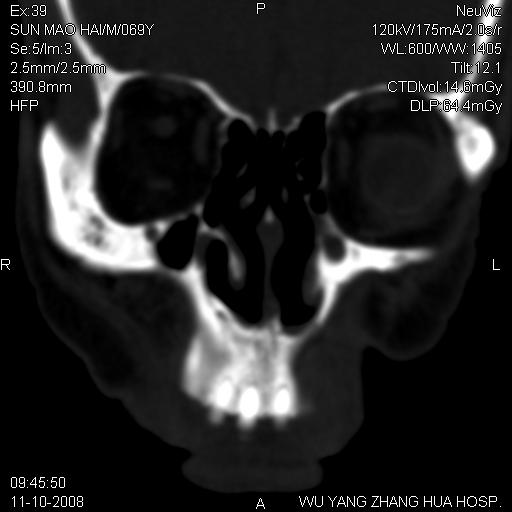

标题: CT16568:右面部瘘管半年余,无其它不适. [打印本页]

标题: CT16568:右面部瘘管半年余,无其它不适.

考虑右上颌异位齿(或斜向阻生齿)并根尖脓肿。

右上颌异位齿(或斜向阻生齿)

1.右上颌异位齿

2.右上颌化脓性骨髓炎

3.右下鼻甲肥大

支持三楼意见。(这种长法还真少见,再长再尖点就成獠牙了。)